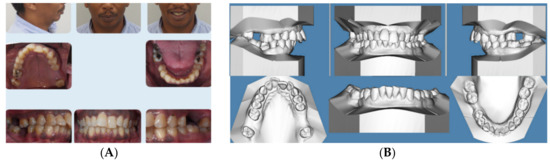

This 28-year-old female presented with the chief complaint that she wanted to correct her crowded teeth (4 mm of crowding in the upper and lower arches) as well as her increased overjet, in addition to improving her convex profile, specifically her recessive chin. Her medical history was noncontributory, clinical records (Figure 1A) showed a convex profile with recessive chin. Intraoral photographs and digital models (Figure 1B) revealed a Class II division 1 subdivision left side (end-to-end left side buccal occlusion) and a right-side Class I. There was increased overjet (5 mm) and average overbite (30%), and her lower midline was deviated 2 mm to the left side. Cephalometric x-ray and analysis (Figure 1C and Table 1) revealed a skeletal Class II apical base relationship (ANB =7.9°) with compensated upper and lower incisors (U1-NA = 90.4° and L1 MP = 90°) (Figure 1C,E), recessive chin, and high mandibular plane angle (FMA = 38.1°). The patient was interested in improving her convex profile without surgical options. She had all third molars removed and no pathology was noted in her cone-beam computed tomography (CBCT)-driven panoramic radiograph (Figure 1D). The patient was provided with Invisalign clear aligners and HFV (VPro5) to use for 5 minutes every day. Additionally, the patient was provided with vertical-pull chin cup (Jaw Bra, Chanhassen, MN, USA) (Figure 1F) to use every night. The patient reported that she was able to change her aligners every 3–5 days without feeling too much pressure upon using new aligners.

Figure 1.

(A) Initial photographs showing the patient’s convex profile with recessive chin and anterior crowding. (B) Initial digital models showing left side Class II buccal occlusion with increased overjet 5 mm. (C) CBCT-driven cephalometric radiograph showing convex profile and recessive chin. (D) CBCT panoramic radiograph showing the patient is missing all third molars; no other noticeable intraoral bony lesion could be detected. (E) CBCT = driven sagittal screen of lower incisor showing its severe proclination with minimum bone appearing on most of the labial surface of the root. (F) A photo of the Jaw Bra (Chanhassen, MN USA). (G) Digital treatment plan (ClinCheck) showing posterior teeth distalization, mesio-bucaal rotation and intrusion to help forward rotation of the mandible to full Class I. (H) Upper arch digital treatment plan (ClinCheck) showing expansion (blue—initial teeth position, white—final teeth position). (I) Lower arch digital treatment plan (ClinCheck) showing expansion (blue—initial teeth position, white—final teeth position) to allow lower incisor intrusion and leveling /alignment of lower incisor crowding. (J) Final photos showing improved patient’s profile and chin projection as well as aligned upper and lower incisors and Class I buccal occlusion both sides. (K) CBCT-driven final cephalometric radiograph showing improved profile and chin projection (L). Final CBCT-driven panoramic radiograph. (M) Final CBCT-driven sagittal screen radiograph of upper and lower incisors showing improved bone labial to both upper and lower incisors. (N) Superimposition of cephalometric tracing of before (black) and after (red) treatment showing improved forward chin projection, palatal root torque of upper incisors, and profile and chin projection and lingual tipping of lower incisors.

After 6 months, the patient finished her active orthodontic treatment, and she was satisfied with overall results. Figure 1J–M show final clinical photos, the lateral CBCT-driven cephalometric radiograph and panoramic radiograph as well as the sagittal screen of upper and lower incisors. Figure 1N shows superimposition of before-treatment and after-treatment cephalometric radiograph tracings. All posttreatment records and Table 1 confirmed improvement of her dental crowding as well as convex profile (ANB = 5°) as well as improvement of her mandibular plan angle (FMA = 35°). Additionally, upper incisor inclination and position relative to SN, NA have been improved close to normal values. In addition, her lower incisor inclination relative to mandibular plane (MP) has been improved (retroclined) to allow the forward position/projection of the mandible. The patient was fitted with four Invisalign Vivera® retainers and was instructed to rotate between them on a monthly basis and to use fulltime for 6 months, in addition to the continuation of using the VPro5 every day as she did during her active treatment period. Then, she was instructed to wear the retainers at night time for the rest of her life as a night guard.